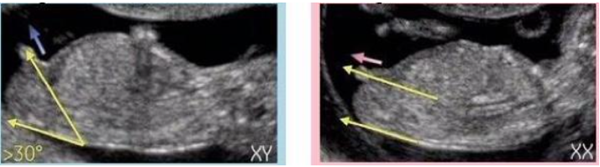

其实NT检查大部分的妈妈都是在孕期12周左右做的,这时候宝宝的第二性征已经发育明显,如果能看到超声的图片,其实是可以看出男女的,我们在图片上可以看到具有性征的一些身体特点,男孩的特征点与身体呈45度角,还多一些,而女孩儿的特征点几乎和躯体平行。还有就是如果是男宝宝,屁股位置会微微上翘,后背脊柱成圆弧状,因为要留空间发育前列腺,相反,女宝宝后背脊柱就相对就平一些。

相对于男孩来说,女孩的脊柱会更平缓一些,但是有的宝宝区别不是很大,也不能绝对的说脊柱更平缓的就是女孩哦。